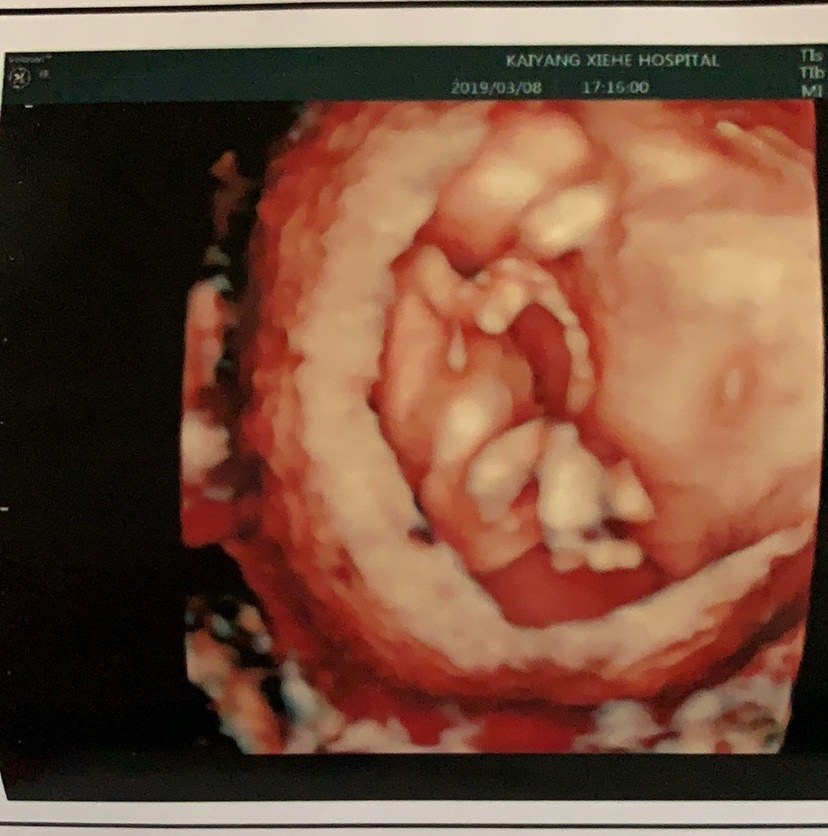

门诊医生看这个单子告诉我说是男宝,不知道准不准

我好像看到小蛋蛋了

好像有小蛋蛋

男

男宝